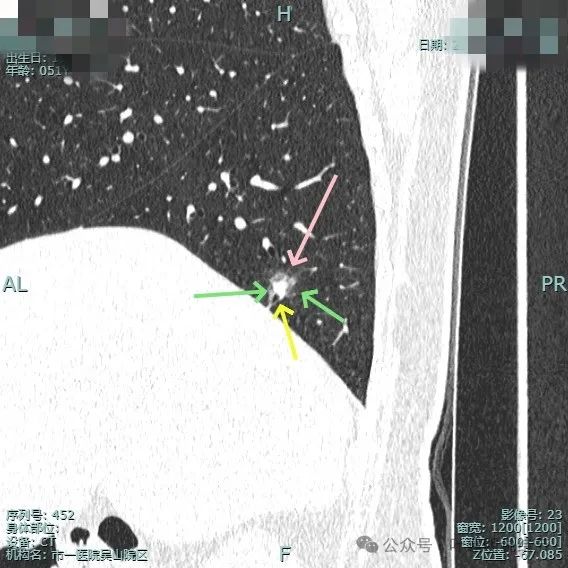

灶边有支气管扩张,表面不平,灶内实性成分无收缩力。

血管进入与异常增粗并散开来(在肿瘤性病变中,这种表现是浸润性而且风险大的表现)。

血管进入穿行并异常增粗,磨玻璃成分显得较为散在,缺乏聚拢性。